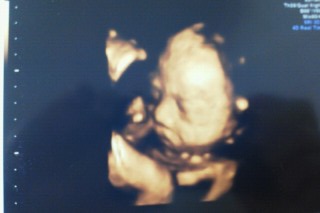

二回目の4D! おーっきなあくび姿を見せてくれました!!!大サービスをしてくれてありがとう(*^^*)可愛かったー♪ 推定体重:840g ちょっと小さめだけどとっても元気な女の子です(^^)!!!